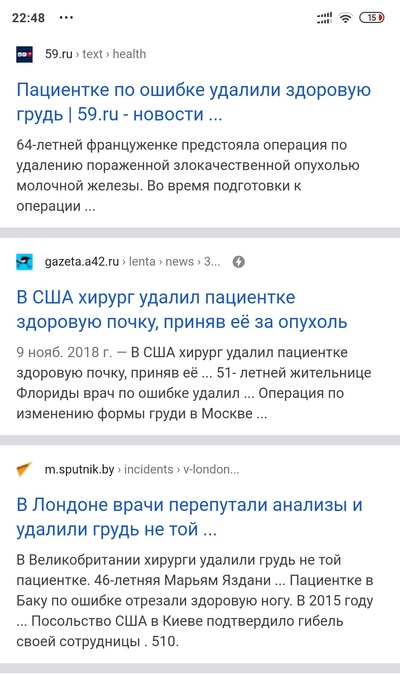

Ну типо уже сто лет как есть специальный рекомендованный воз хирургический чеклист, в котором как-раз всякие тупые вопросы надо галочками отмечать перед операцией. Типо "вы уверены что перед вами лежит нужный пациент", "это точно нужная оперируемая сторона" ну и все в таком духе. Занимает 15 секунд, снижает тупые ошибки на стопитсот процентов.

В июне я сломал шейку бедра, и никаких чеклистов я не видел/не слышал ни в первый раз (когда сверлили голень и ставили растяжку), ни второй (когда собственно вкручивали болты в шейку). Единственное, что было - меня спрашивали "какая нога", ну и медсестра всё равно сначала перепутала левую с правой (ну или посчитала "от себя") но потом увидела, что нога не бритая, и сразу поняла, что правильная нога - другая, я даже не успел возмутиться.

Вообще, правила требуют лечащему врачу перед операцией делать пометки на оперируемой стороне. Это и операционным сёстрам удобнее, и анестезиологу (на какую сторону узнать больного, пока хирург моется)

Когда жили в Германии, была у меня там операция на мениске. Когда положили на операционный стол, спросили, левая ли нога, как в документах? Йодом пометили левую, правую накрыли простынью. Потом еще раз спросили и финальный раз хирург спросил до того, как наркоз дали. В итоге прооперировали ту, которую надо было)

Здесь ставят крестик спецмаркером на конечности, которую будут оперировать. Если не поставили, то хирург имеет право развернуть пациента из операционной, даже если его уже полностью подготовили и он в наркозе (особенно если в наркозе).